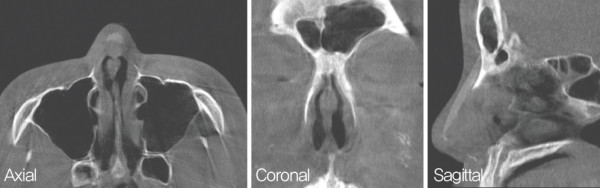

Cottle test에서 우측 positive가 관찰되었으며 흡기 시 좌측 비익연골의 허탈 소견이 보였다. 내원 당시 시행한 CT 검사상 비중격 연골에서 우측으로 만곡된 C-shape deviation이 보였다.

또한 비중격 연골 부분 에 약 4㎜의 천공이 보였으며, 천공 주변의 만성 염증 역시 확인하였다. 비중격 미단부에서 이물질로 보이는 음영이 관찰되었으며 비중격 연장에 사용된 이물질로

판단되었다.

![]()

수술 전 비 내시경. 전체적인 비중격이 우측으로 만곡되어 C-shape deviation을

보인다. 비중격 중간 부분에 천공과 주변으로 만성 염증도 관찰되었다.